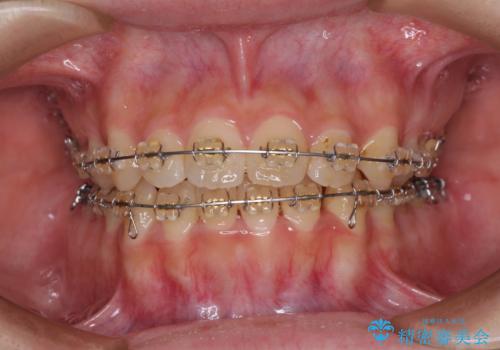

- 大学病院にて装置を装着したものの、治療が十分に受けることができないとのことで転院をされた患者様です。

上顎歯列が前方にあり、口元が閉じにくくなっていたため、既に装着されている装置を使用して上顎歯列全体を後方に移動させていくこととしました。

舌の突出癖があり、それが原因で上下前歯に隙間ができていたため、改善のためのトレーニングを行うように指示をしました。

舌の突出癖の影響か、なかなかスペースが閉じきらず、治療期間は予定よりも長期間となりました。

舌突出癖改善のトレーニングの重要性を認識することとなりました。